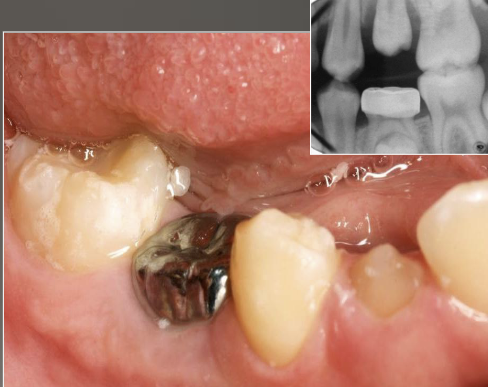

deep surface enamel invagination of the crown or root “tooth within tooth”; can be coronal (most frequent) or radicular

dens invaginatus “dens in dente”

“dens in dente” type I

invagination is confined to the crown

“dens in dente” type II

invagination extends below the CEJ

“dens in dente” type III

invagination may extend through the root

what is the dx?

dense invaginatus